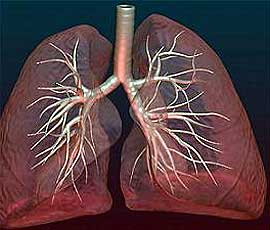

Лечение пневмосклероза заключается в применении лекарственныхЛекарство — природное или синтетическое лечебное средство. растений, обладающих отхаркивающими, противовоспалительными и мочегонными свойствами (читайте статью: лечение хронического бронхита).

Отказ от вредных привычекПривычка — сложившийся способ поведения, осуществление которого в определенной ситуации приобретает для индивида характер потребности. Привычки могут складываться стихийно, быть продуктом направленного воспитания, перерастать в устойчивые черты характера, приобретать черты автоматизма и т. п., закаливание, занятия легкими видами спорта могут значительно улучшить общее состояниеСостояние — физическое самочувствие, а также расположение духа, настроение. больного пневмосклерозом.

В профилактикеПрофилактика — совокупность мер по укреплению здоровья, предупреждению и устранению причин заболеваний человека. Различают индивидуальную и общественную профилактику. пневмосклероза большое значение имеет своевременное и полное лечение простудных заболеваний, пневмоний, бронхитов, а также устранение профессиональных вредностейВредность — вредные для здоровья условия производства. (пыльПыль — мельчайшие сухие частицы, носящиеся в воздухе или скапливающиеся на поверхности чего-либо., вредные газы, облучениеОблучение — воздействие излучений (инфракрасного, ультрафиолетового, ионизирующего) на вещество или биологические объекты с лечебной целью (например, ультрафиолетовая, лучевая терапия), случайное (например, при аварии) и у лиц, работающих с источником излучений.).